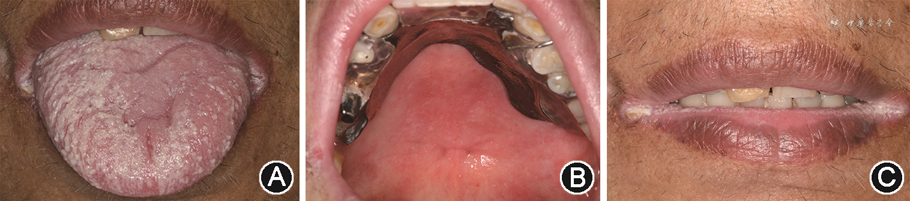

(1)口腔念珠菌病:口腔念珠菌病在HIV感染者的口腔损害中最常见,且常在疾病早期发现,是免疫抑制的早期征象[6]。口腔念珠菌病在临床上常表现为假膜型、红斑型和口角炎3种类型(图1),其中假膜型最常见[5]。假膜型的临床表现为多发性浅表乳白色斑块,可擦掉,无痛,常累及舌、腭、颊、咽等部位(图1A);红斑型表现为大小不一的弥散性红色斑片,伴烧灼性疼痛,多发生于舌背和腭部(图1B);口角炎表现为口角萎缩、皲裂,伴疼痛(图1C),常与假膜型或红斑型同时出现。